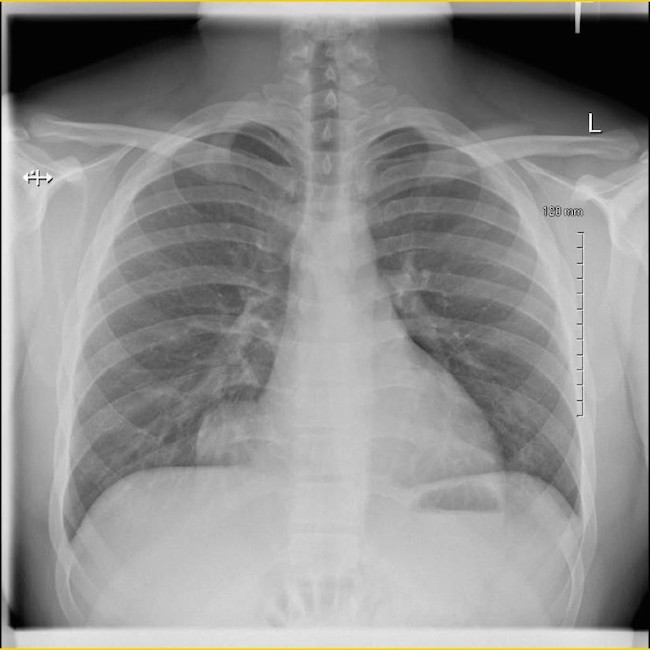

A 19 year old previously healthy male, NCAA defensive end, presents with four months of intermittent, non-exertional, midsternal chest pain and pressure. The pain is described as an episodic band like pressure radiating across the epigastrium. At maximum the pain is rated four out of ten and is completely relieved with holding a deep inspiration. There are no other mitigating or exacerbating factors. There are no other associated symptoms. This has never happened previously. Initial workup in the emergency department with chest radiograph revealed a right cardiophrenic angle mass. Electrocardiogram, complete blood count, comprehensive metabolic panel, lipase and troponin were within normal limits. Computed tomography scan revealed intrathoracic herniation of the left lobe of the liver through a large Foramen of Morgagni hernia over the right aspect of the heart. The patient obtained cardiothoracic surgery consultation and opted to forego surgical intervention while symptoms remained mild to moderate. The patient successfully returned to play and completed a full season as an NCAA defensive end without complication. The patient has another year of eligibility and plans to complete his collegiate career without surgery if symptoms remain stable.